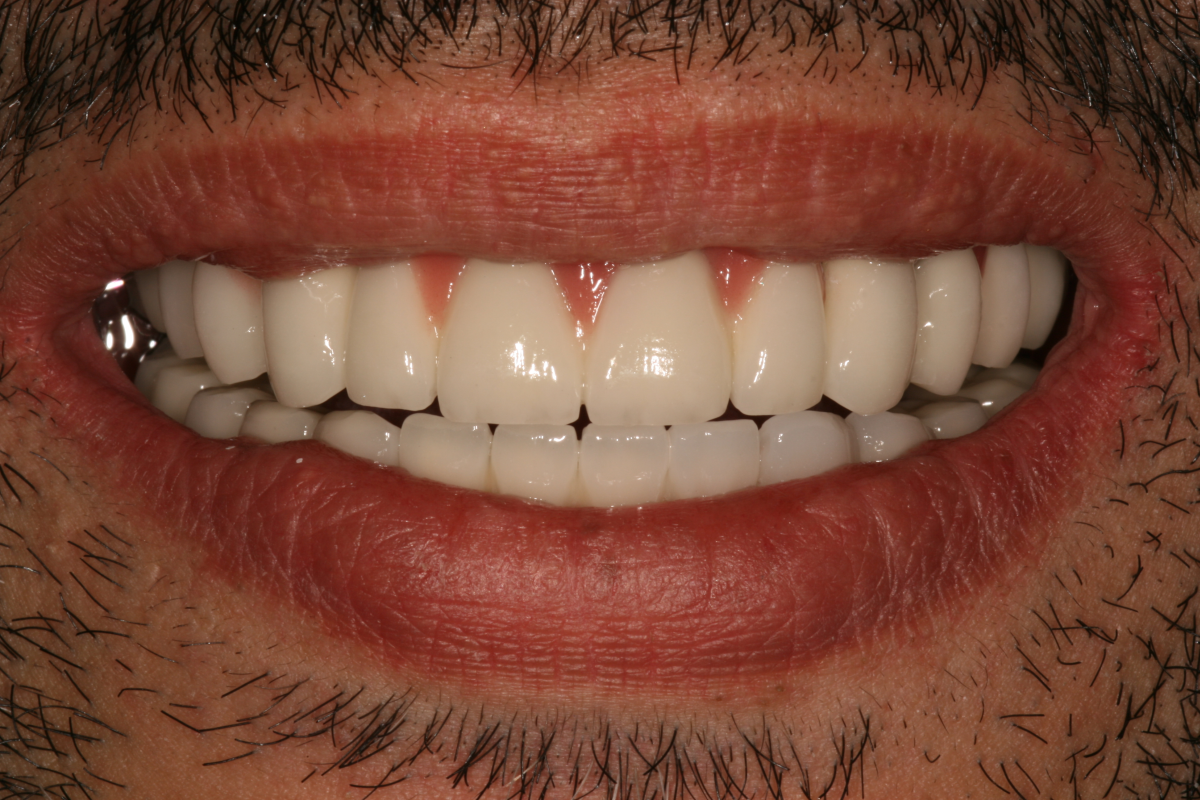

Implantátumok előtte-utána

- A fogászati implantátum természetes hatást kelt, ezért senki sem fogja észrevenni, hogy nem eredetiek a fogai. Még Ön sem fogja érzékelni a különbséget.

Fogászati implantátumok előtte-utána

Implantátum beültetés előtt és után

- Újra természetes, gyönyörű mosoly.